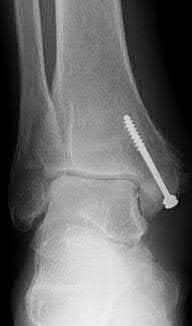

A 28-year-old male sustains a severe hyper-dorsiflexion injury to his ankle in a motor vehicle accident, resulting in a Hawkins Type III talar neck fracture. Which of the following arteries provides the predominant blood supply to the body of the talus, placing it at significant risk for avascular necrosis in this injury?

The artery of the tarsal canal, which is a branch of the posterior tibial artery, provides the dominant blood supply to the talar body. In a Hawkins Type III fracture (talar neck fracture with subtalar and tibiotalar dislocation), the blood supply from the artery of the tarsal canal, the artery of the sinus tarsi, and capsular vessels are disrupted, leading to an avascular necrosis (AVN) rate approaching 100%.